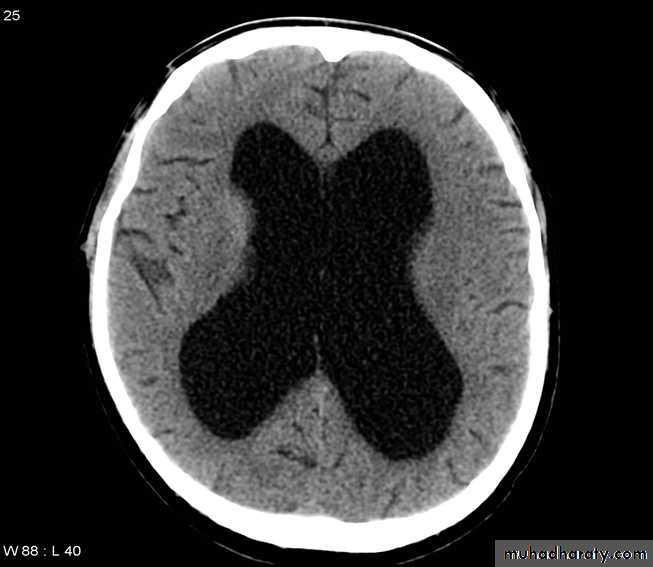

Hydrocephalous

2 typesObstructive ( non – communicating )

Non –obstructive ( communicating )

No obstruction of the ventricular pathway , but the absorption of the csf at the level of arachnoids' granulation is occluded secondary to lodge by blood clot or inflammatory cell or infection post meningitis most commonly to occur post SAH .